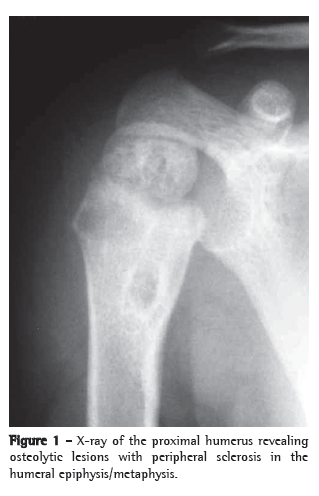

Case reportA 21-month-old boy, born in São Paulo, presented with fever and mild functional impairment of the right upper limb. The child had daily episodes of fever (> 38°C), predominantly at night. One week prior, the child had started presenting pain upon palpation and upon movement, as well as limited movement of the right arm. The mother stated that the boy had no history of local trauma. An X-ray of the right upper limb revealed a lytic lesion of the proximal epiphysis/metaphysis, with ill-defined borders, surrounded by a halo of reactive bone sclerosis, periosteal reaction and soft tissue edema (Figure 1). Magnetic resonance imaging revealed areas of abnormal marrow signal and soft tissue edema with highlighting of the infected marrow by the contrast medium-signs consistent with osteomyelitis of the proximal humerus (Figure 2). The patient received cephalosporin for 10 days in an outpatient setting. On day 8 of the antibiotic therapy, the child came to our facility due to fever and persistent pain.

On X-rays, lytic lesions with a sclerotic halo can be seen, as can periosteal reaction and periarticular osteoporosis.(4,9-11) Histopathological studies show granulomatous inflammation with epithelioid cells, with or without caseous necrosis. Acid-fast bacilli are detected in approximately half of all cases, and most present strongly positive PPD reactions.(9,12)

Lytic and sclerotic bone lesions with periosteal reaction characterize the radiographic lesions. In the case described here, the CT findings in the epiphysis, the metaphysis and the diaphysis were consistent with previous descriptions in young patients. Older children usually present only metaphyseal changes.(4)